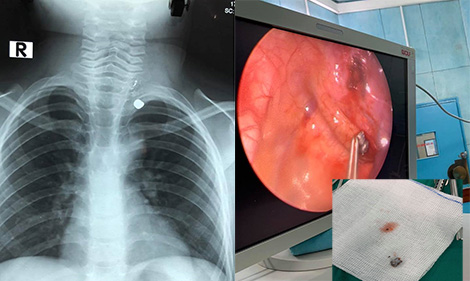

Bé trai suýt mất mạng vì bố bất cẩn trong sử dụng súng

Vụ việc xảy ra tại Đắk Lắk. Sau khi đi săn về, người bố bất cẩn để khẩu súng vẫn còn đạn bên trong phía trước nhà, 2 con trai của của anh 6 và 9 tuổi đùa nghịch, bóp cò khiến đạn bắn xuyên từ cổ vào ngực người em.